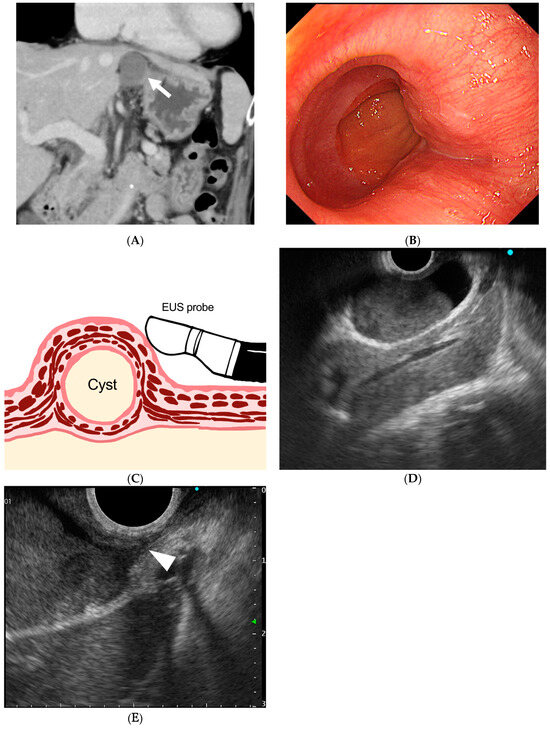

Figure 1. (A) Coronal section of contrast-enhanced computed tomography (CT). A 3 cm homogeneous mass with well-defined margins and a uniform interior near the gastroesophageal junction with a median Hounsfield unit value of 42.1, which was higher than the water density. (B) Endoscopic view of the esophagogastric junction reveals a 3 cm mass with normal surface mucosa and a gently rising mass on the mouth side of the esophagogastric junction. (C) Schematic diagram of esophageal duplication cyst and EUS probe. The cyst and the attachment site to the esophageal wall were observed using EUS. (D) Endoscopic ultrasonographic image. A 28 mm unilocular cystic lesion is visualized, with internal heterogeneous hypoechoic components suggestive of debris. Endoscopic ultrasonography (EUS) was performed using a curved linear echoendoscope (GF-UCT260; Olympus Corporation, Tokyo, Japan) connected to an ultrasound scanning system (EU-ME2; Olympus Corporation, Tokyo, Japan). (E) Magnified image of the area where the cyst wall is in close proximity to the esophageal wall. The cyst wall shows a layered structure, and the hypoechoic layer, presumed to be muscular, is partially continuous with the external longitudinal muscle of the esophagus (white arrow). Esophageal duplication cysts are characterized by cystic structures that possess a two-layered muscular wall similar to that of the esophagus and are attached to the esophageal wall [1]. Most cases present as unilocular lesions containing serous fluid, although debris may also be observed [2]. Differential diagnoses include bronchogenic cysts, gastrointestinal stromal tumors, neurogenic tumors, lymphangiomas, and pseudocysts. On EUS, key diagnostic features include continuity with the esophageal muscularis propria, a layered cyst wall, and a fluid-filled internal component. The absence of cartilage further supports the diagnosis of an esophageal duplication cyst. In the present case, imaging studies, including EUS, confirmed the cystic nature of the lesion, demonstrated a double-layered cyst wall, and revealed its attachment to the native esophageal muscle layer. These findings contributed to an accurate preoperative diagnosis.